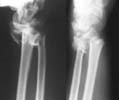

40 year old bank clerk fell down from a height and suffered this closed injury to the dominant upper limb. On presentation he had numbness in the fingers pertaining to the median nerve area. Since there was a suggestion of nerve compression I have initiated the initial treatment. Would like to get your views on management. I will present what I have done after the discussion.

Attaching the initial X-ray.